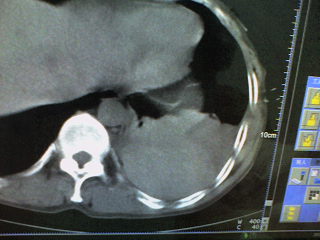

患者,男 51岁。突发性胸痛来诊。

肝囊肿 脾大 腹水

病变是胸腔内的。前部液体引出来的是血红色的液体。现在鉴别其后缘的高密度是什么?

这是一例胸膜外血肿形成的病例啊。。后面的高密度为凝血块。

手术证实的。